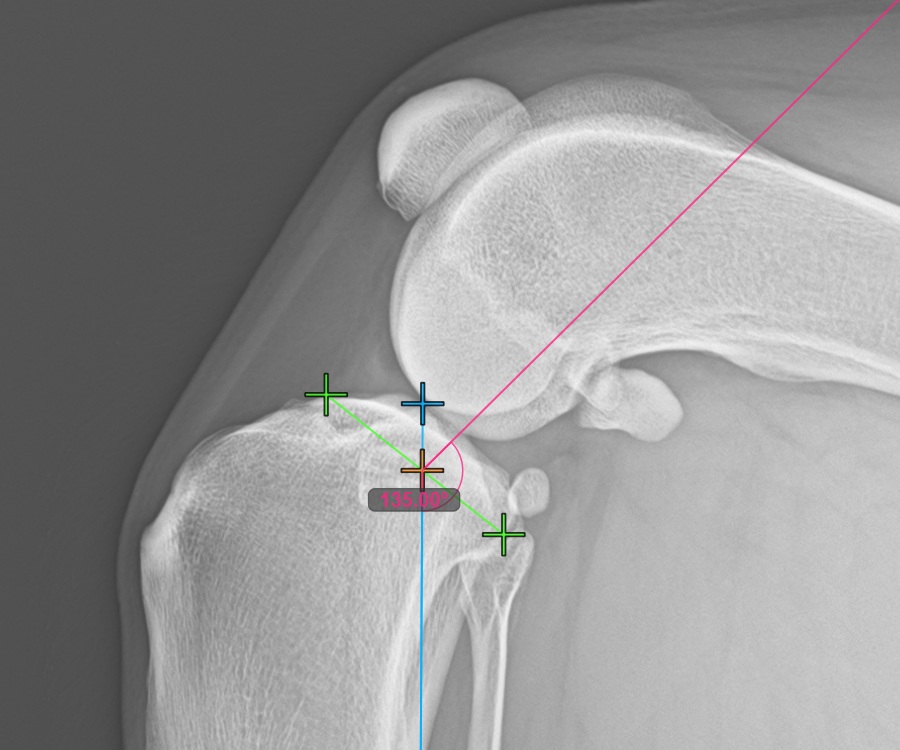

Markieren Sie den hintersten Punkt des Tibiakopfes, um die Messung fortzusetzen. Zusätzlich zeichnet die Software automatisch eine feste Winkelmessung von 135°, wobei der Schnittpunkt zwischen der Längsachse der Tibia und der Linie, die den vordersten und hintersten Punkt verbindet, als Scheitelpunkt des Winkels dient.

Das Bild unten zeigt die übliche Platzierung des hintersten Punkts am Tibiaplateau.